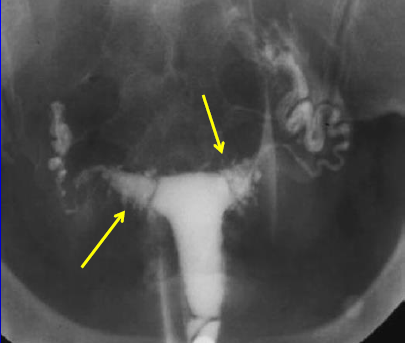

Endométriose

FELLAH L. - UCL

Année académique 2021-2022

Imagerie de la femme DES SPECIALITE